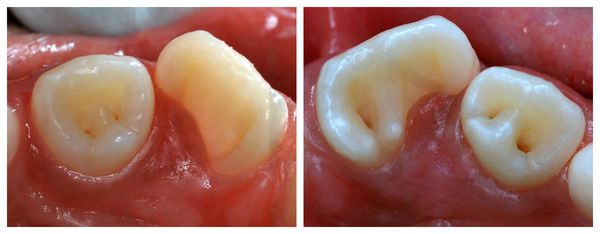

Leczenie kompleksowe zrośnięcia zębów

2. Fuzja i zrośnięcie zębów (fuzja, zrastanie zębów)

Podejrzenie fuzji pojawia się, gdy podczas leczenia ortodontycznego ząb nie reaguje na siły przesuwające lub podczas ekstrakcji stawia nietypowy opór. W takich przypadkach wykonuje się zdjęcie rentgenowskie (radiogram), które potwierdza zrost korzeni.

Leczenie obejmuje:

• dewitalizację (leczenie kanałowe, usunięcie miazgi) – gdy połączenie obejmuje tkanki zęba;

• chirurgiczne rozdzielenie korzeni (separacja korzeni) – jeśli to możliwe technicznie i funkcjonalnie.

Po zabiegu powierzchnie zębów zabezpiecza się materiałem kompozytowym lub koroną, aby przywrócić estetykę i funkcję.